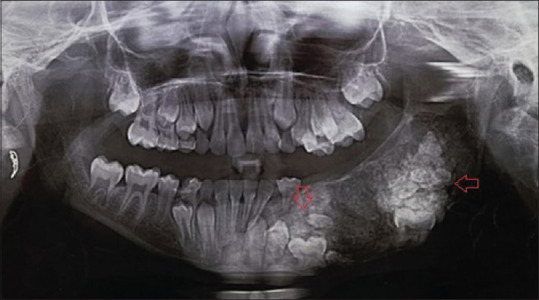

Rationale: Odontomas are benign, asymptomatic odontogenic tumours, while ossifying fibromas are fibro-osseous lesions from the periodontal ligament. The rare transition from odontomas to an ossifying fibroma in the same jaw highlights the need for long-term follow-up.

Patient concerns and diagnosis: A young adult with multiple odontomas, one of which later changed into a different type of bone-related tumour; ossifying fibroma. The first odontoma was surgically removed 10 years ago, followed by the development of a cemento-ossifying fibroma from an anterior odontoma.